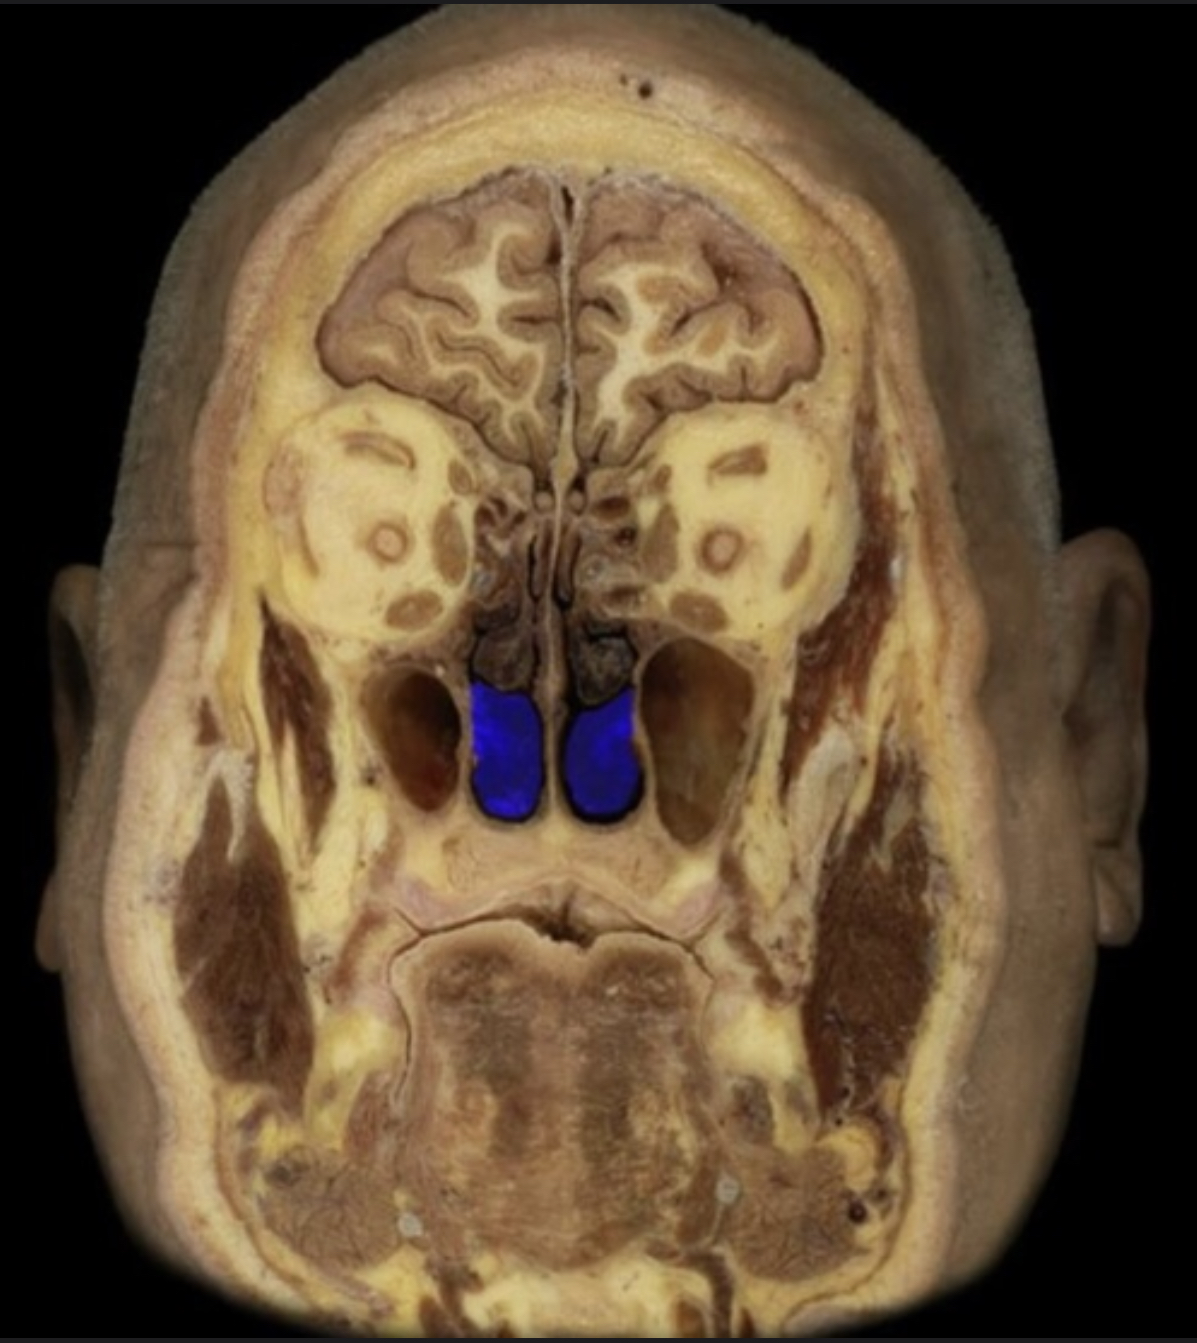

What structure is highlighted in blue?

External naris